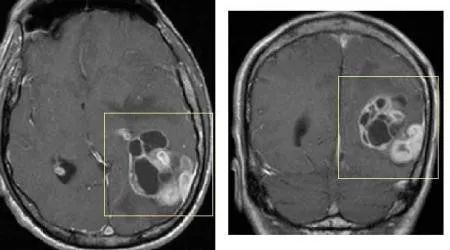

神经胶质瘤(画框所示)的MRI影像学图片

目前认为,MRI是确诊脑胶质瘤的主要检查手段。若MRI仍然难以确诊,PET/CT是一个很好的补充检查措施。